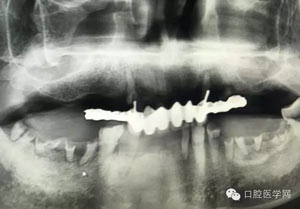

病例1:患者迫切希望保留自己的這一顆牙齒,根尖周陰影比較大,二度松動.而且旁邊有種植修復(fù)體,和患者溝通好后,治療好后觀察一個月后冠修復(fù),因為有種植的后期修復(fù),所以有了機會觀察,術(shù)后三個月和術(shù)后四個月,根尖恢復(fù)的還算不錯,希望能夠繼續(xù)觀察下去.這樣子的病例,做的時候我們一定要非常的小心,和患者要有充分的溝通以及不同科室的溝通然后決定怎么樣做比較好,假如就是出現(xiàn)了問題,到時候我們也比較好處理些,免得我們自己到時候不好收場。